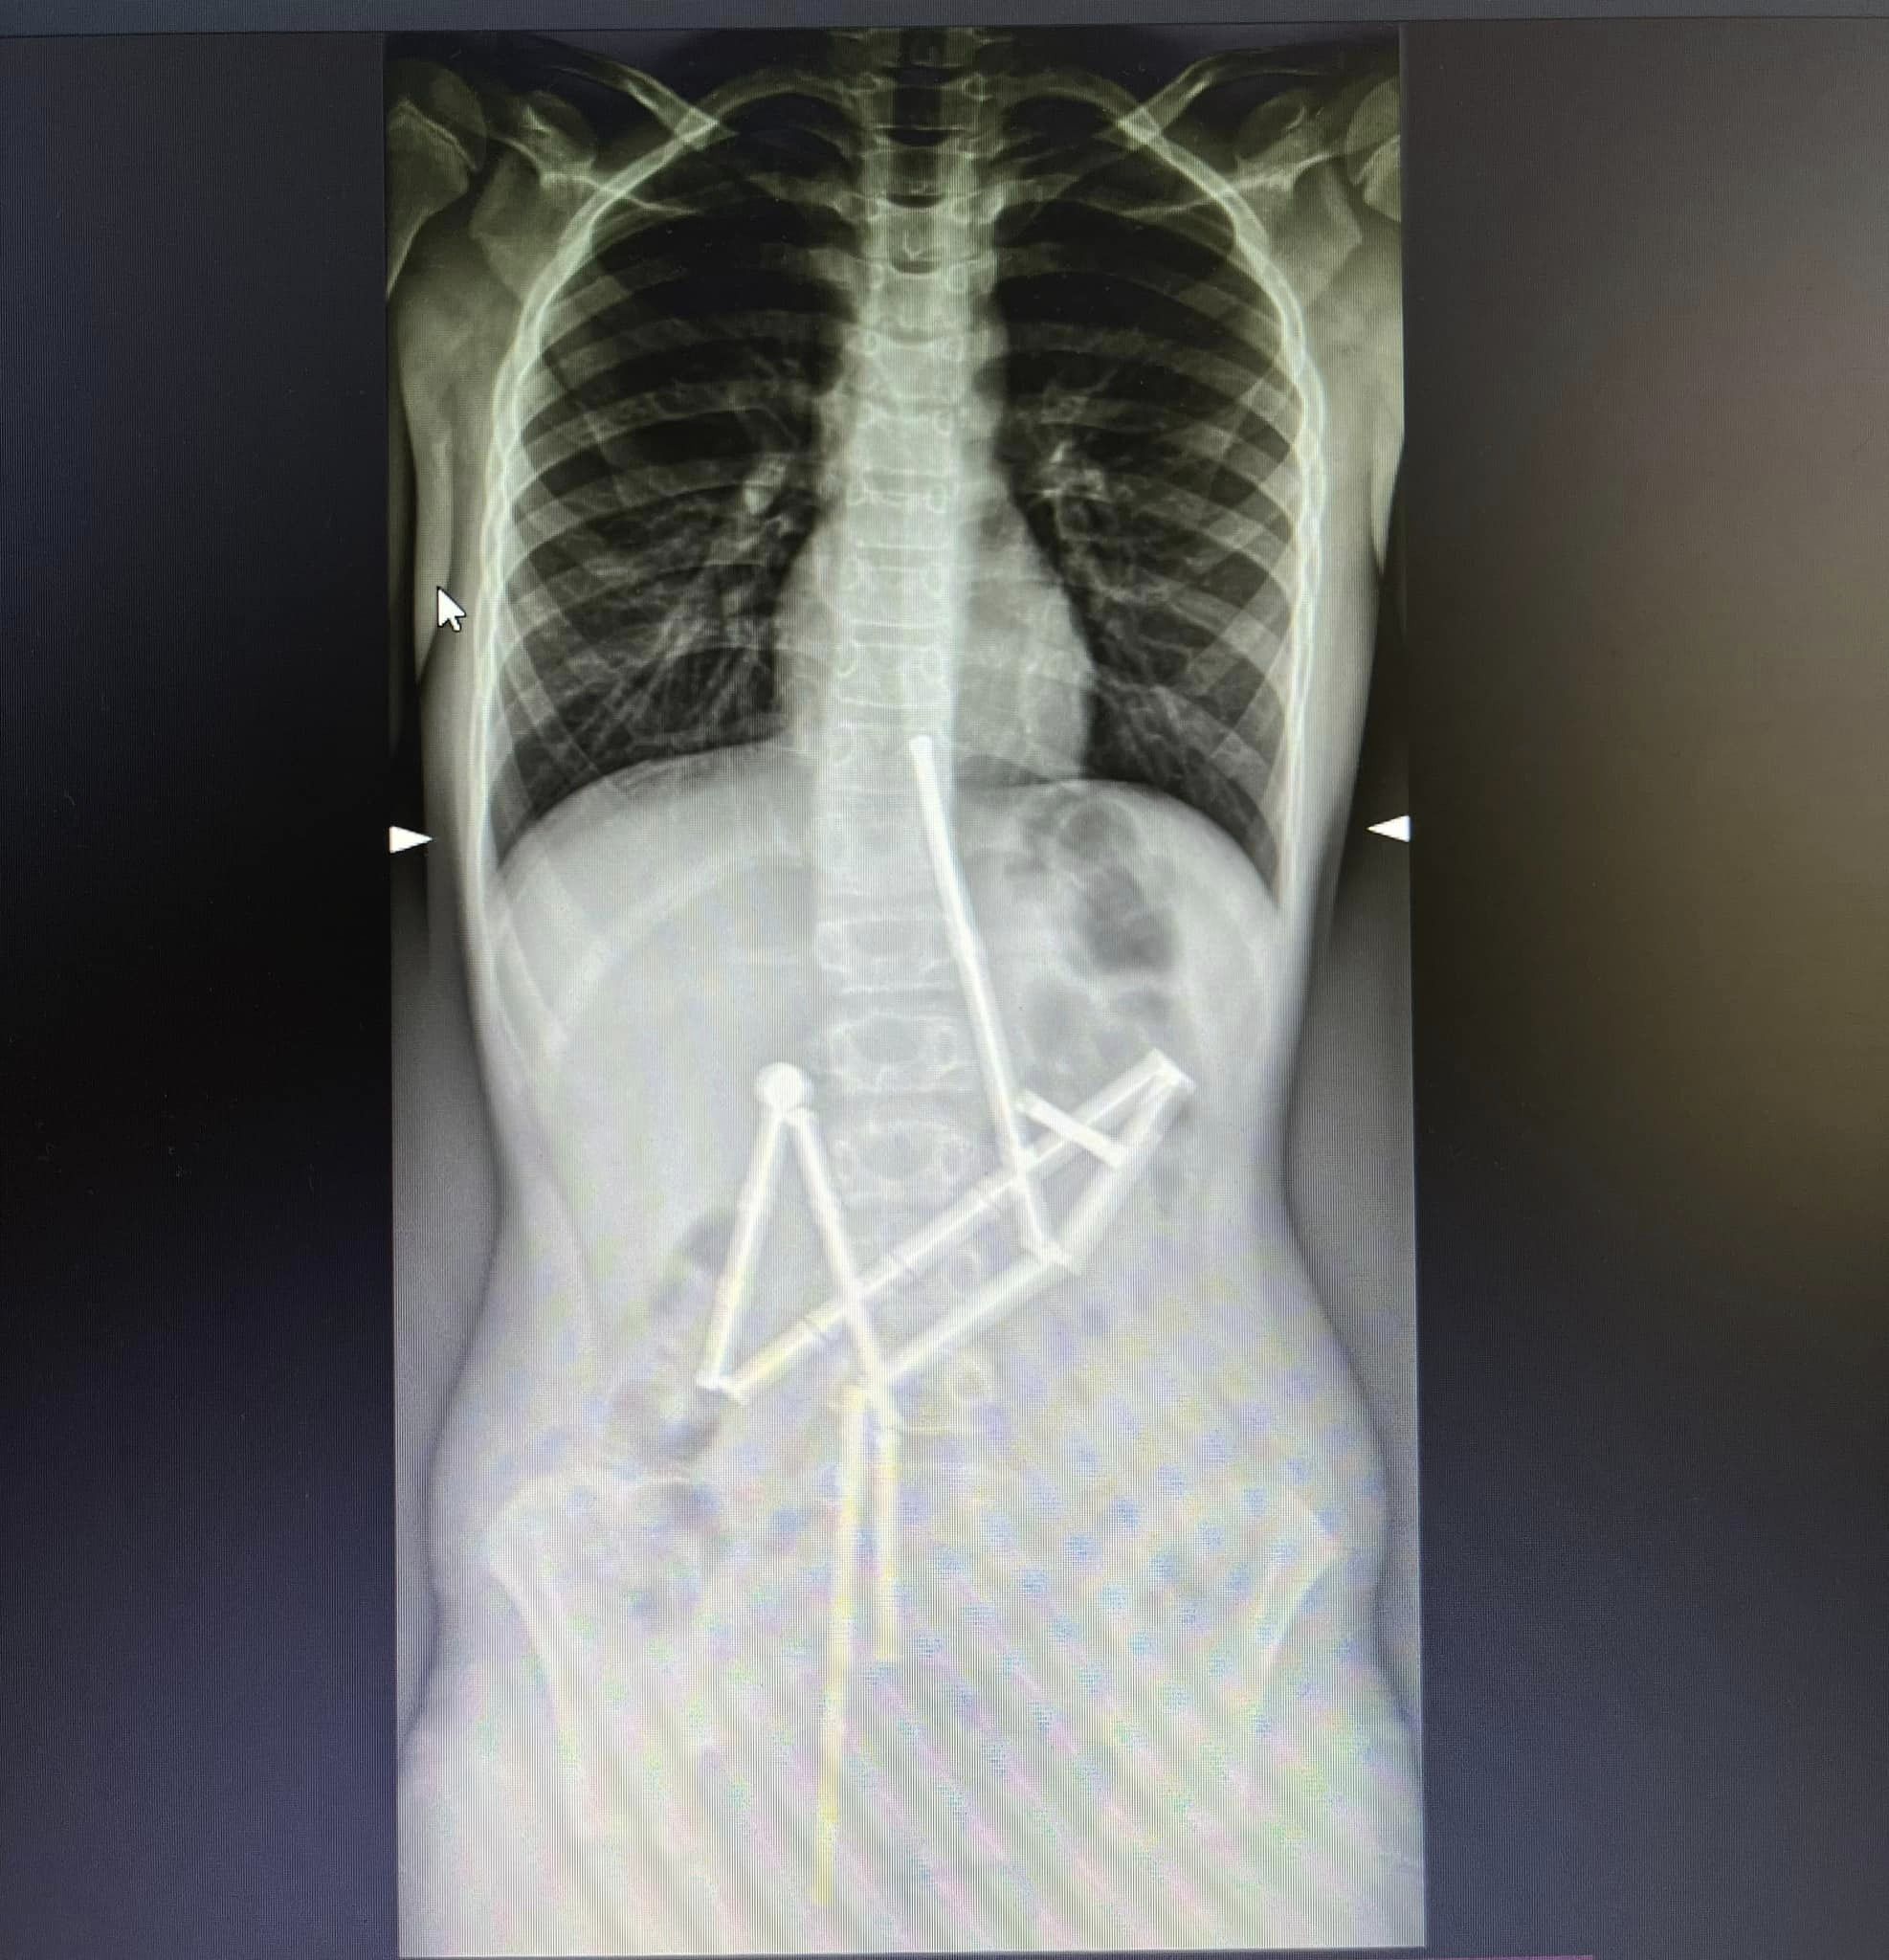

Вже на першому рентген-знімку спеціалісти побачили наявність у травному каналі цілої групи сторонніх тіл, у яких вдалось впізнати магнітний конструктор. 20 магнітів знаходились у різних частинах шлунково-кишкового тракту, проте були зʼєднані між собою.

Консиліумом лікарів було прийняте рішення про проведення невідкладного оперативного втручання, адже кожна година очікування могла погіршити стан пацієнта. Відмінність магнітів від інших сторонніх тіл, які можуть проковтнути діти, полягає у їх притягненні один до одного та защемленні тканин. Як наслідок, виникають зони некрозу (змертвіння), перфорації порожнистих органів, шлунково-кишкові непрохідності тощо.

Бригада анестезіологів якнайшвидше ініціювала передопераційну підготовку та введення в наркоз. Першою до роботи долучилась команда спеціалістів відділення ендоскопії. Вони провели дослідження слизових оболонок стравоходу, шлунку та дванадцятипалої кишки (езофагогастродуоденоскопія) та оцінили стан верхніх відділів травного тракту, виявили проковтнуті обʼєкти, що були зчеплені між собою. Медикам вдалося захопити перший магніт і витягти його разом із ланцюжком з 18 елементів конструктора.

Проте один магніт залишився, й спеціалісти не мали змоги видалити його ендоскопічно. Надалі за операційним столом почали працювати хірурги. Була виконана лапаротомія та ретельна ревізія органів черевної порожнини. Під час цього в дитини було виявлено 5 перфоративних отворів та останній елемент конструктора. Всі отвори були закрито, а магніт видалено.